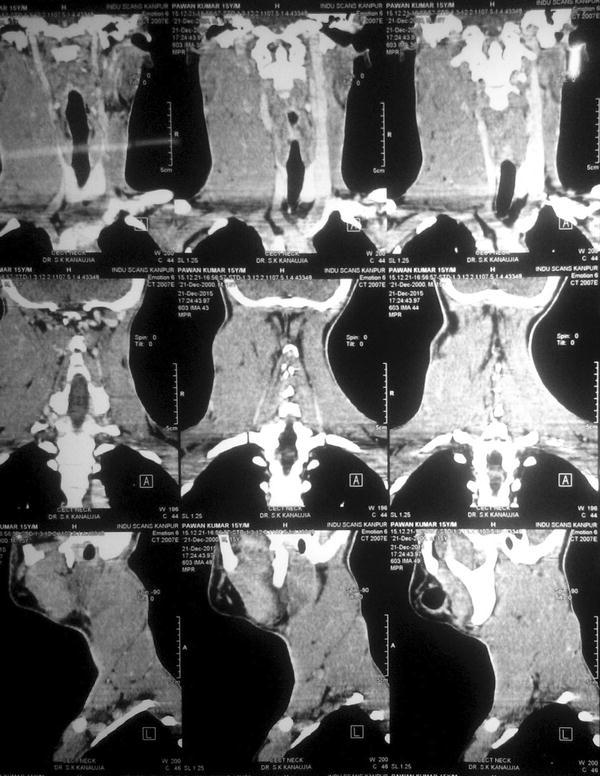

A fifteen year old boy was presented to our hospital with chief complaints of painless progressive swelling in the right side of neck in last 6 months. Patient was having no history of fever, pain in throat, difficulty in deglutition, difficulty in respiration, chronic cough, loss of appetite or loss of weight. On examination there was non-tender, non-fluctuant soft to firm swelling involving anterior and posterior triangle of neck about 10 × 6.5 cm in dimension on right side. It was mobile and not adherent to underlying skin (Figs. 1, 2). There was also swelling involving bilateral supraclavicular region. There was no any swelling in axillary or inguinal region. On nasal endoscopy no abnormality was detected. Routine haematological examination showed Haemoglobin 12.2 g%, Total leukocyte count 6.3 × 109/litre, Erythrocyte sedimentation rate 15 mm 1st hour while differential leukocyte count was with in normal limits. Mantoux test was negative. High resolution Ultrasonography suggested multiple discrete, homogenous lymph node in right carotid space. There was no cystic necrotization, calcification or loss of fibrofatty plane are seen (Fig. 3). Contrast enhanced computed tomogram neck with thorax suggested a large lobulated soft tissue lesion about 10 × 6.5 × 5.5 cm in dimension (Fig. 4). No intratumoral necrosis was seen. Patchy heterogeneous enhancement was seen in post contrast images. Mass was mildly compressing trachea and right thyroid gland to the left (Figs. 5, 6). Bilateral supraclavicular lymph node was seen along with non-necrotic lymph node in superior mediastinum. Fine needle aspiration cytology from cervical lymph node was highly suggestive of Rosai–Dorfman disease, however biopsy was advised for confirmation. Biopsy was done under local anaesthesia from the posterior triangle of neck just behind the mid part of sternocleidomastoid muscle. Histopathology showed diffuse effacement of lymph node architecture and dilated sinuses distended with benign histiocytes (Figs. 7, 8); the diagnosis was given as sinus histiocytosis with massive lymphadenopathy (Rosai–Dorfman disease). This patient was put on oral prednisolone 10 mg three times a day in tapering doses for 21 days initially and then on low dose of steroids for next 4 months. The patient showed marked clinical improvement.

Fig. 4.

CT scan coronal view